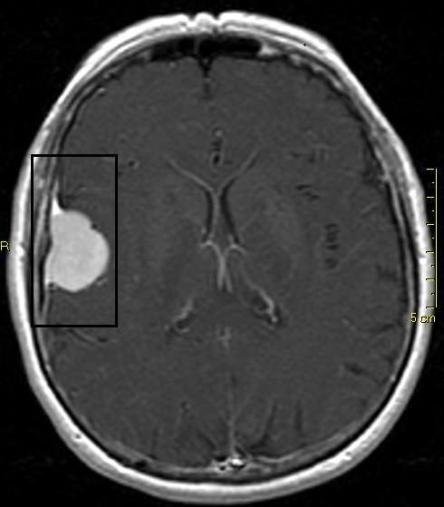

Nach einer kurzen Bedenkzeit entscheiden sich die Besitzer, nun weitere Abklärungen vorzunehmen, und Schnurrli wird an die neurologische Abteilung des Tierspitals Bern überwiesen. Eine Magnetresonanzuntersuchung des Kopfes zeigt, dass die Katze an einer grossen Krebsgeschwulst in der linken Hirnhälfte leidet, welche auf das Hirngewebe drückt. Am Wahrscheinlichsten handelt es sich dabei um einen (in der Regel gutartigen) Tumor der Hirnhaut, ein Meningeom.

Das Meningeom ist der häufigste primäre Hirntumor bei Katzen und Hunden. Es stellt eine Entartung der Meningen, also der das Hirn und das Rückenmark umhüllenden Hirnhäute, dar. Sie sind meistens gutartig (d.h. sie wachsen nicht in das umliegende Gewebe ein oder bilden Ableger) und wachsen langsam. Die Symptome entwickeln sich aufgrund des ständig zunehmenden Druckes auf das im Schädel eingeschlossene Hirn und können zu Beginn sehr subtil sein (Wesensänderung, vermehrtes Miauen oder Kratzen am Kopf). Zur Diagnose ist idealerweise ein MRT oder allenfalls ein CT notwendig; auf einem normalen Röntgenbild ist der Tumor meist nicht zu erkennen.

CT (Computer-Tomogramm) und MRT (Magnet-Resonanz-Tomogramm) sind moderne bildgebende Verfahren, bei welchen das Zielgebiet quasi in Scheiben geschnitten und so dreidimensional dargestellt werden kann (altgriechisch "tomo" = "Schnitt", "graphein" = "schreiben"). Beim CT wird dazu die altbewährte Röntgentechnik benutzt, indem die Röntgenröhre spiralig um das Zielgebiet geführt wird und dabei unzählige Aufnahmen macht. Eine CT-Aufnahme dauert kürzer als ein MRT, verursacht aber eine Belastung mit Röntgenstrahlen. Beim MRT wird ausgenutzt, dass die Atomkerne des Gewebes einen sogenannten Kernspin und damit ein kleines Magnetfeld besitzen. Mittels eines von aussen kurzfristig zusätzlich angelegten Magnetfeldes können aufgrund der folgenden Veränderungen der Ausrichtung der Atomkern-Magnetfelder im Zielgebiet Rückschlüsse auf den jeweiligen Gewebetyp gezogen werden. Die verschiedenen Gewebetypen werden als unterschiedliche Graustufen dargestellt. Bei beiden Untersuchungen muss der Patient absolut still liegen; entsprechend werden Tiere dazu in Vollnarkose versetzt.